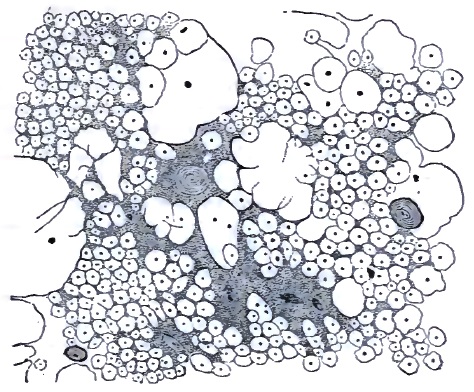

| 31. | TRANS-SECTION OF UPPER LUMBAR CORD OF A PATIENT MODERATELY ADVANCED IN TABES DORSALIS |